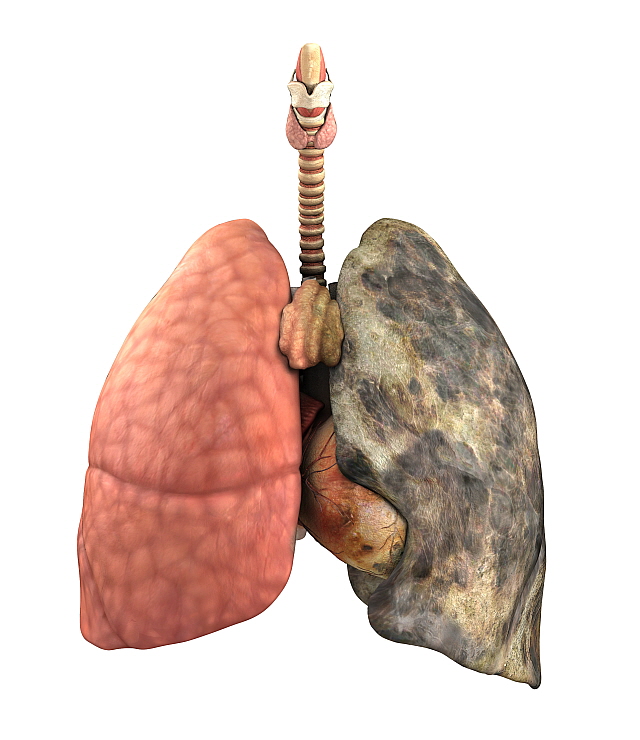

폐렴 증상 9. 입술이나 손끝이 푸르스름하게 변색 (청색증)

산소 포화도가 낮아지면서

입술, 손톱, 발끝이 보랏빛 또는 푸르스름하게 변하는 청색증이 생길 수 있습니다.

이는 폐렴이 상당히 진행된 상태일 수 있으므로 응급 상황입니다.10. 구토, 설사 등 소화기 증상